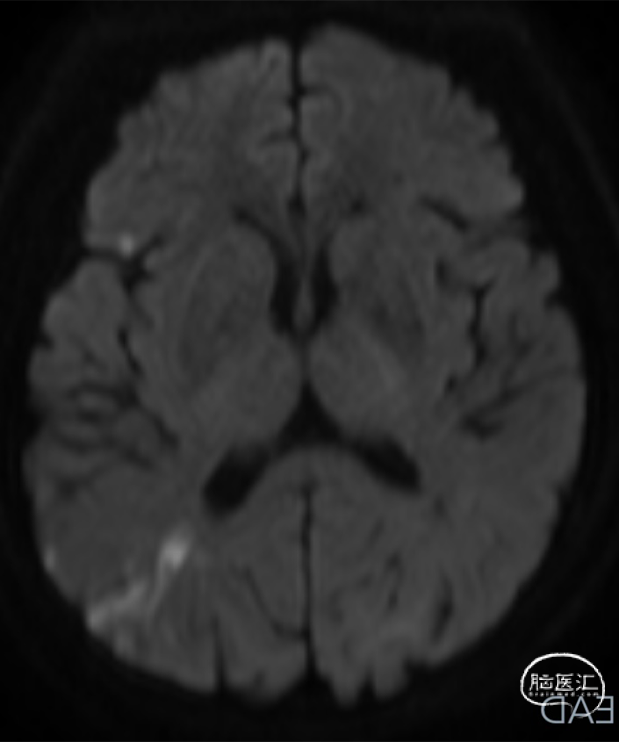

➤2024.3.20 头颅MRI

左侧基底节区/侧脑室旁及额顶枕叶急性期脑梗死。